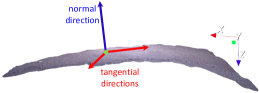

Another effective way to perform real-time dense reconstruction is to combine sparse SLAM and stereo vision, the idea of which is closely related to the famous KinectFusion work [35], which merges the raw depth map provided by Microsoft Kinect to generate the fine models. It is a natural idea to replace the depth map with the results of stereo matching. However, the most difficult part is to align the depth map by SLAM, and KinectFusion is based on the ICP method. However, due to the narrow field of view and the smooth surface of tissue, ICP-based alignment cannot achieve accurate registration in the tangential directions.

The second term of (18), , aims to minimize the distance between the existing 3D model and the current stereo matching model at key frame , which is

| (19) |

where are points of the existing model, and are points of the current stereo matching model that has the same re-projection pixel coordinate with . is Tukey’s penalty function to handle outliers. if has a valid depth, otherwise . is the normal direction of obtained from the stereo matching point cloud, which allows the template to ’slide’ along the tangent directions, as shown in Fig. 4.